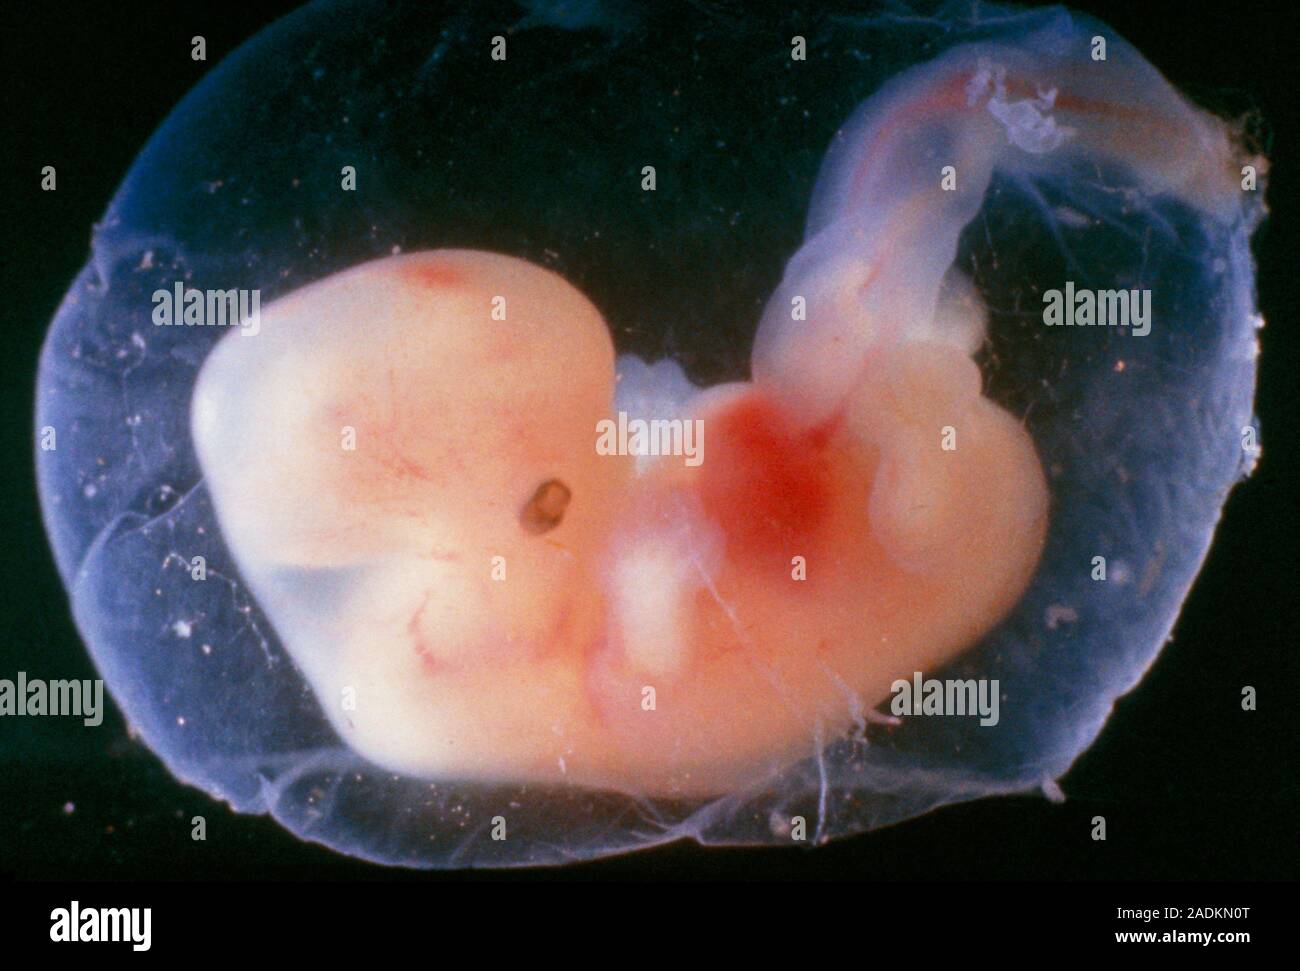

Удивительные фотографии эмбриона на 8 неделе беременности